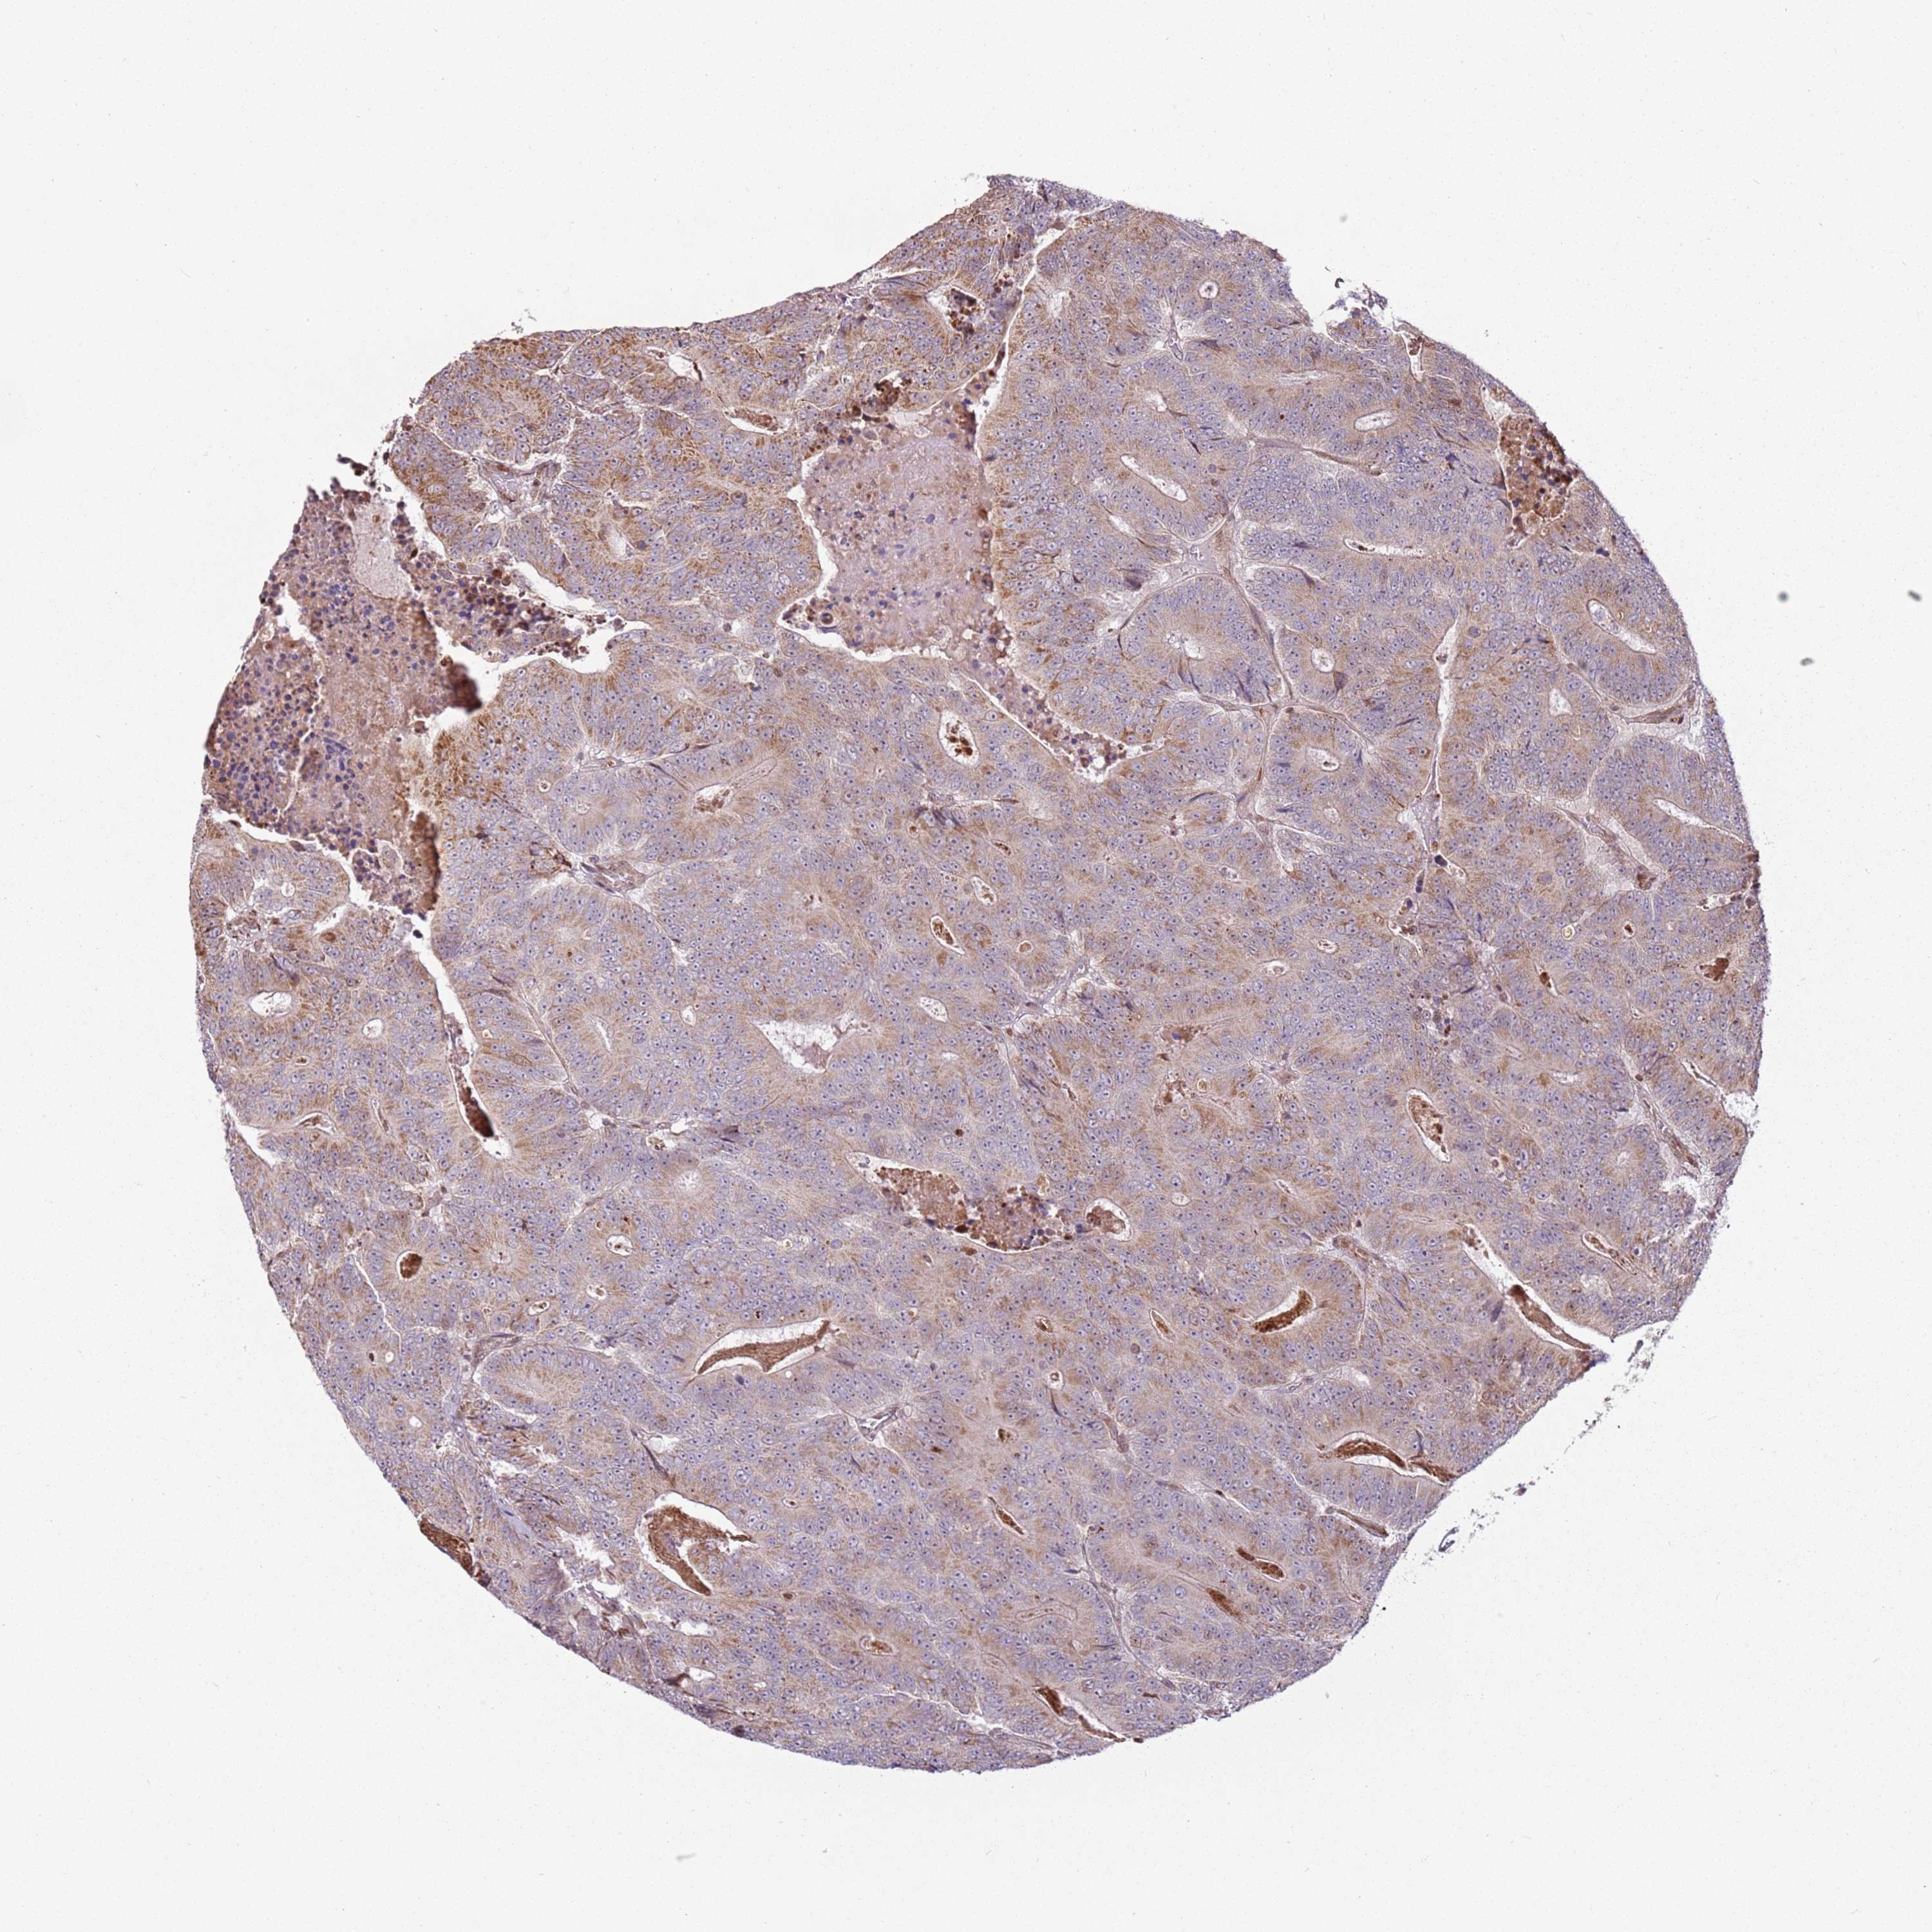

CANCER COLORECTAL CANCER Show tissue menu

Colorectal cancer

Human cancer

Colon adenocarcinoma